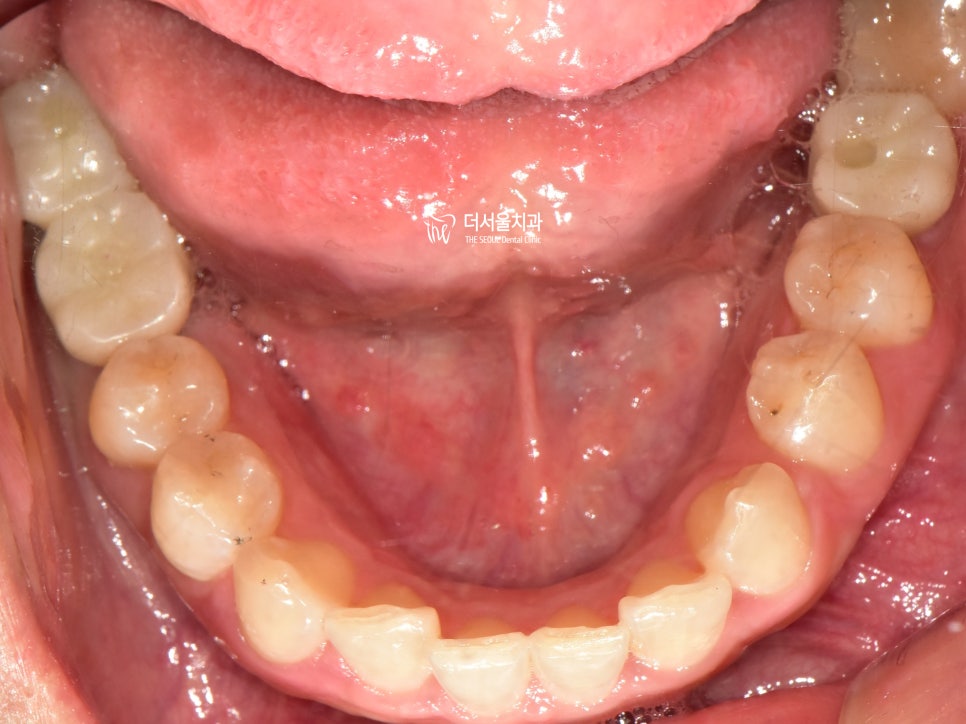

지르코니아로 제작된 크라운을 올려드린 모습입니다.

교합은 물론이며 주변에 있는 인접치들과

잘 어울리고 있는 모습이죠~?

다행히 환자께서는 두가지 모두

만족할만한 결과를 안겨드릴 수 있었네요.